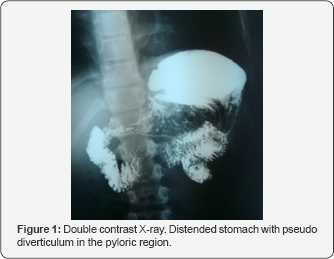

A 8, 5-year-old boy presented with a history of abdominal pain, nausea, vomiting, heartburn, dysphagia and anorexia. He suffers from asthma and allergy and has been treated with inhaled corticosteroids, long-acting inhaled beta 2-agonists and antihistaminics from 3 years. Physical examination showed slight growth retardation (hight <0,9SD); microcephaly (head circumference <1,5SD); facial asymmetry with characteristic facial changes prominent on the right side, such as: triangular face, downward slanted palpebral fissures, ptosis, low-set ears with thickened helices; webbed neck on the right side, scapula alata on the right side, scoliosis, heart murmur and bradycardia. Laboratory findings, which included white blood cell count, red blood cell count, transaminases, amylase clotting tests and stool examination, were normal. 24-hour pH monitoring showed mild gastroesophageal reflux. Esophageal manometry demonstrated esophageal motility disturbances, with the presence of more than 45 % of simultaneous contractions in the distal esophageal body and low-amplitude esophageal peristalsis. Ultrasonography revealed two structures in the gallbladder fossa. The presumptive diagnosis of gallbladder duplication was made. Repeated ultrasonography showed two gallbladders with two separate cystic ducts. Gastroscopy showed septum in stomach fundus, wide open pylorus, duodenal malformation, with suspicion of duodenal duplication or duodenal diverticulum and two separate duodenal papillas. Upper gastrointestinal tract radiographic examination with contrast established the diagnosis of duodenal duplication. Contrast enhanced computer tomography of the abdomen revealed the presence of annular pancreas, separated inferior part of the spleen and confirmed the diagnosis of gallbladder and duodenal duplication. Magnetic resonance cholangiography (MRCP) was made to establish the type of gallbladder duplication and to demonstrate the presentation of bile and pancreatic ducts. Because of small caliber of the cystic ducts and their openings exact determination of the type of gallbladder duplication was not possible. The evaluation of MRCP was also difficult because of abnormal anatomic presentation of the pancreas and duodenum. Since the child still suffered from abdominal pain and vomiting preparations for surgery were made. To preoperatively well establish the anatomic presentation of the gastrointestinal malformation endoscopic retrograde cholangiopancreatography (ERCP) was performed. Catheterization of one of the duodenal papillas, localized on the edge of the wide open pylorus, showed short pancreatic duct with small pancreas. Catheterization of another duodenal papilla, localized in duodenum showed two gallbladders, laying side by side. The bile outflow from both of them was good (Figure 1).